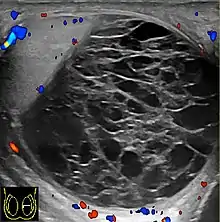

Fig. 10. Epidermoid cyst. Onion peel appearances of the tumor together with absence of vascular flow are typical findings of epidermoid cyst.

Epidermoid cysts, also known as keratocysts, are benign epithelial tumors which usually occur in the second to fourth decades and accounts for only 1–2% of all intratesticular tumors. As these tumors have a benign biological behavior and with no malignant potential, preoperative recognition of this tumor is important as this will lead to testicle preserving surgery (enucleation) rather than unnecessary orchiectomy. Clinically, epidermoid cyst cannot be differentiated from other testicular tumors, typically presenting as a non-tender, palpable, solitary intratesticular mass. Tumor markers such as serum beta-human chorionic gonadotropin and alpha-feto protein are negative. The ultrasound patterns of epidermoid cysts are variable and include:

However, these patterns, except the latter one, may be considered as non-specific as heterogeneous echotexture and shadowing calcification can also be detected in malignant testicular tumors. The onion peel pattern of epidermoid cyst [Fig. 10] correlates well with the pathologic finding of multiple layers of keratin debris produced by the lining of the epidermoid cyst. This sonographic appearance should be considered characteristic of an epidermoid cyst and corresponds to the natural evolution of the cyst. Absence of vascular flow is another important feature that is helpful in differentiation of epidermoid cyst from other solid intratesticular lesions.